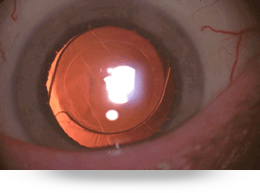

La catarata es la opacidad del lente intraocular natural llamado cristalino, el cual es normalmente transparente actuando como un lente de una cámara, enfocando la luz en la retina.

El único tratamiento para la catarata es la cirugía ocular, extrayendo el cristalino opaco e implantado un lente intraocular artificial; está indicada cuando la persona ya no puede realizar sus actividades cotidianas como conducir, leer, ver computadora o desplazarse con seguridad.

Existen diferentes tipos de lentes intraoculares como mono focales que solo corrigen la visión lejana y los multifocales que corrigen tanto la lejana como la cercana.